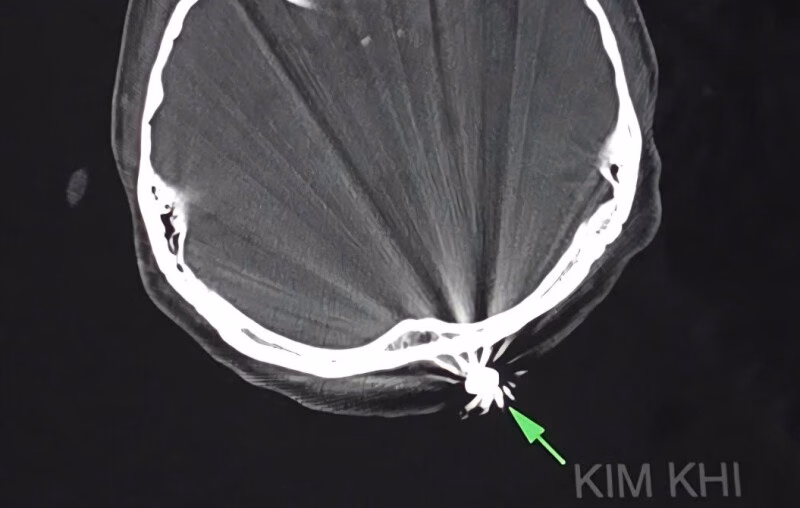

Cán bộ y tế Bệnh viện đa khoa Trung ương Cần Thơ vừa thực hiện ca phẫu thuật thành công, giúp một người phụ nữ 40 tuổi thoát khỏi nguy hiểm sau khi bị trúng đạn.

Chị D.T.K.T, cư trú tại TP Cần Thơ, gặp tai nạn khi đang làm vườn tại nhà vào chiều ngày 28/7. Viên đạn đã găm vào vùng chẩm của chị, gây ra tình trạng chảy máu nhiều. Bệnh nhân được đưa đến bệnh viện trong tình trạng đau đầu, với vết thương vùng chẩm khoảng 1cm đã cầm máu.

Các bác sĩ thuộc Khoa ngoại thần kinh đã nhanh chóng tiến hành phẫu thuật để lấy dị vật và xử trí tổn thương. Quá trình phẫu thuật, các bác sĩ đã mở rộng vết mổ khoảng 3cm để lấy ra dị vật kim khí là đầu đạn có kích thước 0,5×0,3cm. Ca phẫu thuật kéo dài khoảng 45 phút và diễn ra rất thuận lợi.

Điều đáng chú ý trong trường hợp này là viên đạn chỉ xuyên qua lớp da, chạm nhẹ vào xương chẩm mà không gây tổn thương đến não và các cấu trúc lân cận. Hiện tại, bệnh nhân tỉnh táo, tiếp xúc tốt, vết mổ khô và không ghi nhận triệu chứng thần kinh khu trú.

BSCK2 Chương Chấn Phước, Trưởng khoa ngoại thần kinh, Bệnh viện đa khoa Trung ương Cần Thơ, cho biết vết thương do hỏa khí thường rất phức tạp. Chúng có thể gây tổn thương kết hợp nhiều cơ quan, dễ nhiễm khuẩn và khó đánh giá chính xác mức độ tổn thương qua bề mặt.

Trong trường hợp của bệnh nhân T., viên đạn đã gần hết quỹ đạo bay nên lực xuyên giảm đáng kể. Nhờ đó, vết thương chỉ giới hạn ở phần mềm nông và không gây nguy hiểm đến tính mạng. Đây là một ca phẫu thuật thành công, thể hiện sự chuyên nghiệp và nhanh chóng của đội ngũ y bác sĩ tại Bệnh viện đa khoa Trung ương Cần Thơ.